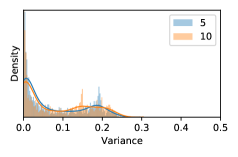

5.1 Distribution of Uncertainty Scores

Distribution of Uncertainty Scores Across Different Severity Levels As explained in Section 3, each uncertainty metric essentially defines an order/ranking among the data points. We conducted an analysis to better understand what data will be assigned high uncertainty under a particular uncertainty metric . Picking out the highest ranked data points (), we calculated the ratio of data points from each SL. Figure 4 summarizes the results as box plots for the Kaggle-DR and the Messidor-2 datasets; additional detailed statistics can be found in Table S.1 in the supplementary materials. From the plot and table, SL1 & SL2 examples account for a higher proportion among the top-ranked uncertain examples across the three ensemble methods. This finding matches our intuition that incipient disease examples (SL1 & SL2) are more likely to be considered uncertain by ensemble methods due to their ambiguity.

In contrast, the MC-dropout method showed the worst overall performance among the three, as it can be seen from the high ratios of SL0 examples among the uncertain negatives in Figure 4. The histograms in Figure 2 provides another perspective to look into the phenomenon, where a decent proportion of MC-dropout model’s predictions on SL0 inputs entailed low confidence (far from 0 or 1), which from another angle explained why MC-dropout was less specific in terms of lower FNP; many no-DR inputs (i.e. SL0) were erroneously assigned high uncertainty by MC-dropout models.

As discussed in Section 5.1 and Section 5.3 in the main paper, the mean metric and the stacking ensemble will have better performance in the precision (specificity) on the ambiguous data. Here, more detailed results are shown in Figures S.3 & S.6 and Table S.1. Figures S.3 & S.4 show the histograms of the uncertainty score for Kaggle-DR and Messidor-2 datasets that are the in-distribution (i.d.) dataset in our experiment and FigureS.5 & S.6 show the histograms for ImageNet and CIFAR-10 datasets, which is the o.o.d. datasets in our experiment. Each group of histograms contains results from the three evaluated ensemble methods (stacking ensemble, MC-dropout and TTA) and the three uncertainty metrics (mean, var and kl). Additional detailed results not displayed in Figure 4 can be found in Table S.1, which shows the proportion of the data of different SLs varies across different . For comparison, we also included in Table S.1 the results from single learners, and the proportions of data of different SLs (before any selection was made).